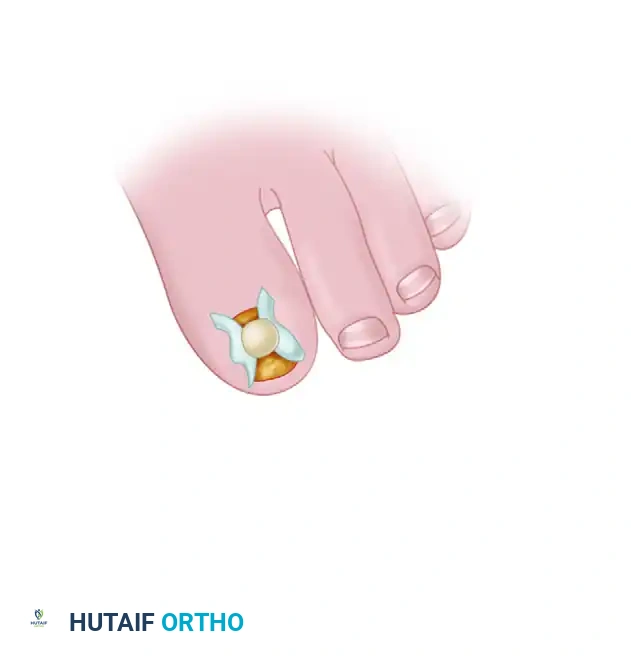

1. Incision Design: Make an inverted L-shaped incision around the nail. The short leg of the "L" should run parallel to, and 5 mm distal to, the distal edge of the nail (hyponychium). The long leg of the "L" should run 5 mm medial or lateral to the nail fold, extending proximally past the nail matrix, usually reaching the level of the distal interphalangeal (DIP) joint.

2. Flap Elevation: Create a full-thickness flap down to the bone. Sharply and meticulously elevate this flap off the distal phalanx. It is critical to elevate the flap without penetrating or injuring the overlying nail matrix.

3. Tumor Identification: Reflect the skin and matrix flap dorsally and inspect the deep (volar) surface of the flap. The glomus tumor is usually obvious within the sub-matrix tissue, appearing as a ball-shaped or egg-shaped, opaque, semi-elastic, bluish-red structure.